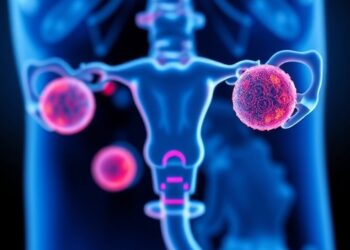

Insilico Medicine Names ISM6200 as a Promising Best-in-Class Selective NR3C1 Inhibitor for Ovarian Cancer, Cushing’s Syndrome, Obesity Linked to Hypercortisolism, and Glaucoma

In a groundbreaking stride forward in the realm of therapeutic innovation, Insilico Medicine, a clinical-stage company harnessing the power of ...